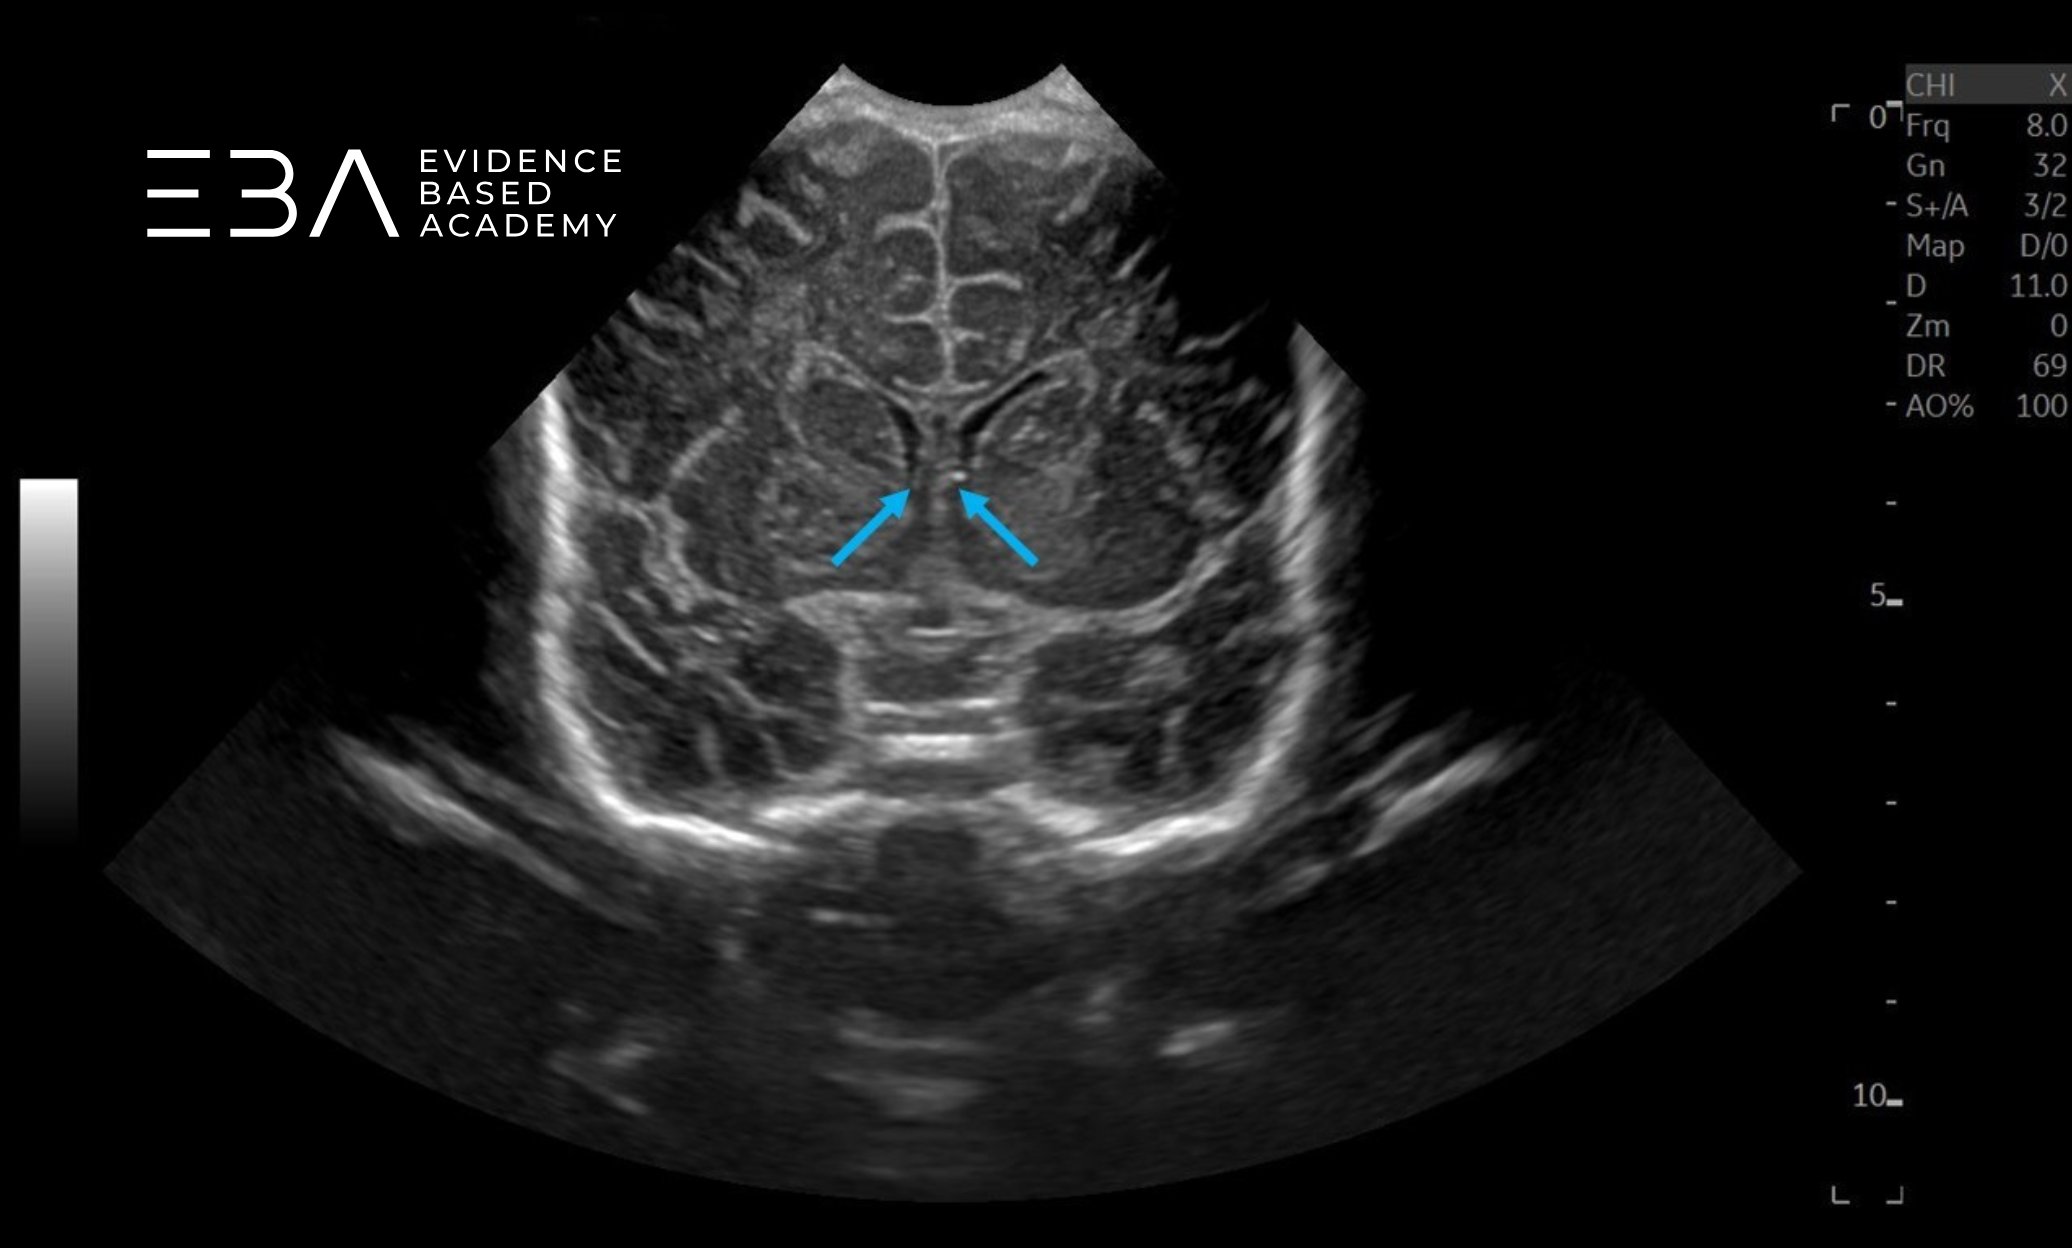

zdj. 0

Głowica sektorowa. Strzałkami zaznaczono półkule móżdżku. Słaba jakość obrazu struktur położonych blisko głowicy.